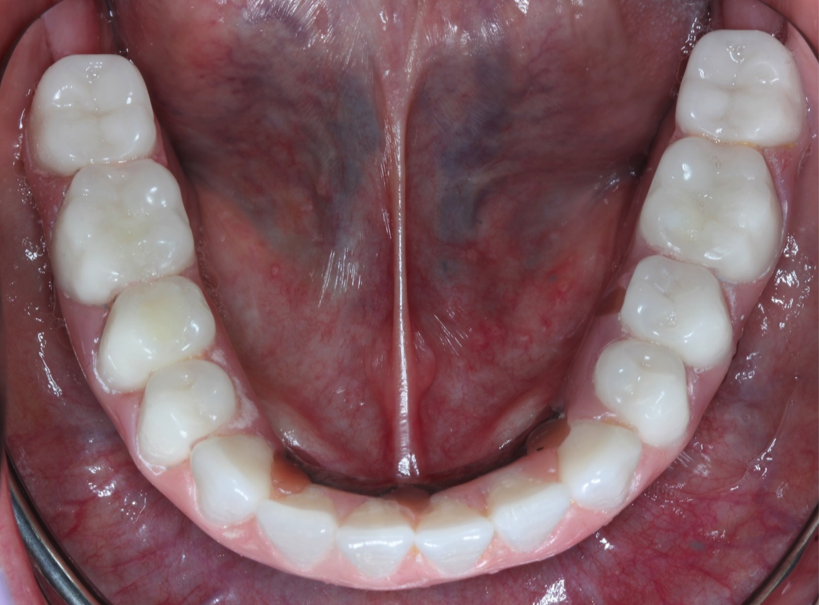

Fixed Implant Bridge

This is what we can do for you! This patient came to us with a few teeth that had crowns that were in bad shape and failing. We placed several implants in his bottom jaw and made him an implant bridge that restored all his teeth. Can you see the difference in how his teeth look?. We also had to fabricate him some gum tissue to make up for the amount of bone and gum he had previously lost.